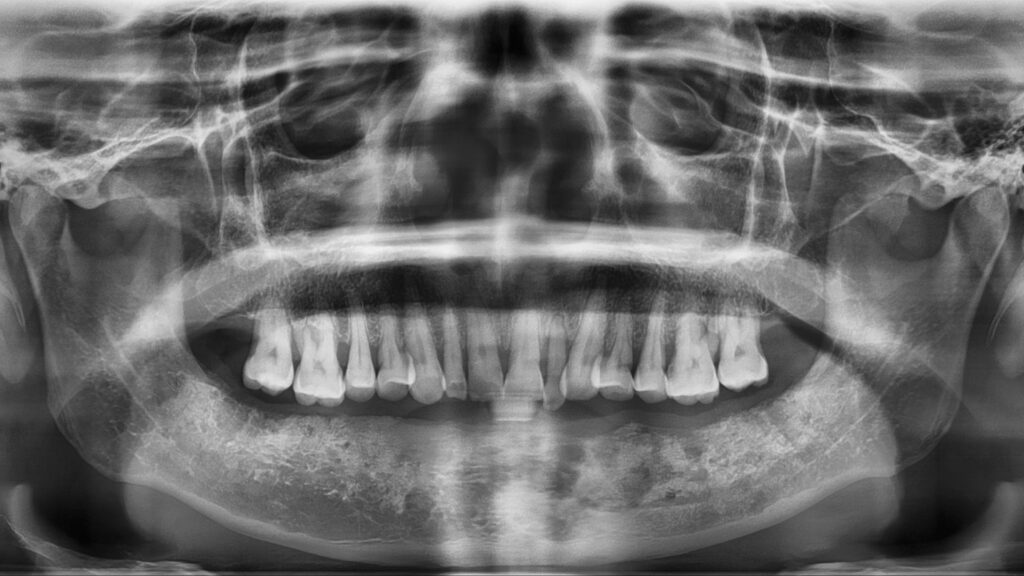

La reconstrucción dental es uno de los tratamientos más versátiles y resolutivos en odontología moderna. Cuando un diente se ha fracturado, debilitado o presenta una caries extensa, disponer de un procedimiento que permita devolverle su forma, su función y su […]